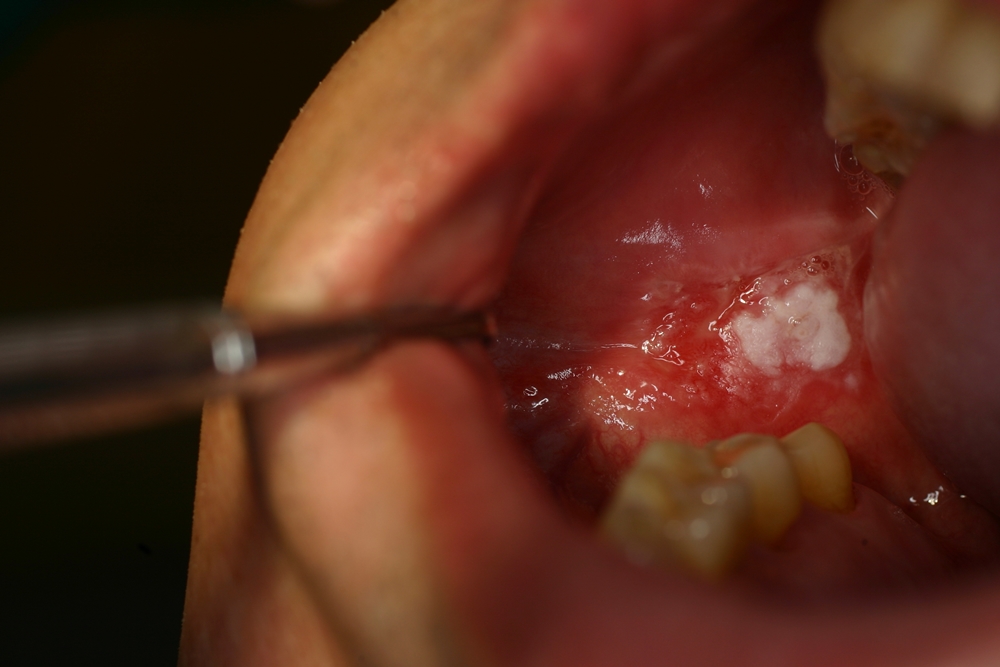

2.紅板症

ビロード様の鮮紅色を呈する平坦な病変に対する臨床診断名で、白板症に比べて、癌化率も高く(40〜50%)、口腔底、頬粘膜、舌に好発します。

>>紅板症症例写真